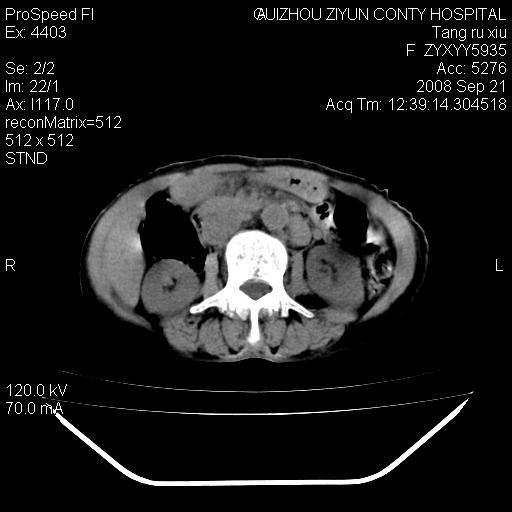

f、57岁,上腹痛.2月,近来胸闷。2月前在外院摄胸片示左侧胸腔少量积液。

肝脏大小形态尚可,其实质内可见多发大小不等的低密度影,边缘模糊。肝门区结构紊乱,腔静脉腹主动脉旁可见多发软组织密度影,部分融合成团块状,并向下延伸。胰腺及十二指肠结构显示不清。腹腔内脐后肠管走形僵硬,管壁可见增厚。盆腔内可见多个淋巴结影。所扫层面左侧胸腔可见大量弧形水样密度影,其内侧可见被压缩的肺组织影。左侧胸壁可见一小结节样软组织密度影,边缘模糊。心脏纵隔向右侧移位。心脏包膜内可见囊样低密度影,其内侧心房室周围可见一圈气体样密度影。纵隔内大血管旁可见多发软组织团块影,部分融合。

1.腹膜后淋巴瘤侵及肝脏,肺内及纵隔内多发转移。2.左侧大量胸腔积液并压缩性肺不张。3.心包脓肿可能,转移不除外。4.脐后局部肠管管壁增厚,考虑炎症可能,肿瘤不除外。